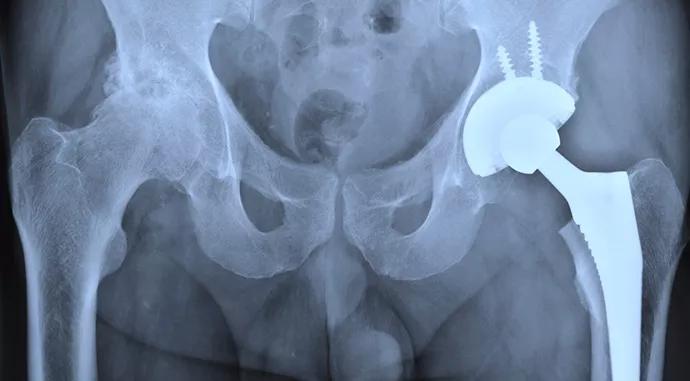

Joint replacement is one of the most effective procedures in medicine, reliably relieving pain and restoring function. With demand for joint replacement expected to continue to rise significantly in the coming decades, the concern is that the associated costs will outpace the ability of our stretched system to afford this demand.

To that end, Euclid Hospital, one of the community hospitals in the Cleveland Clinic health system, is collaborating with CMS to deliver innovative care under the BPCI initiative for MS-DRGs 469/470, primary total hip and knee arthroplasty. We believe that several factors have fully aligned Euclid Hospital with the BPCI initiative and prepared it to achieve the BPCI objectives: (1) our physician-led, group-model culture and strategy; (2) our operational capabilities and infrastructure; and (3) our clinical redesign initiatives and track record. A few of these factors merit additional discussion.